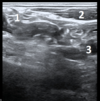

what are these things in the right groin (left is medial, right is lateral)

1. femoral vein 2. femoral artery 3. femoral nerve